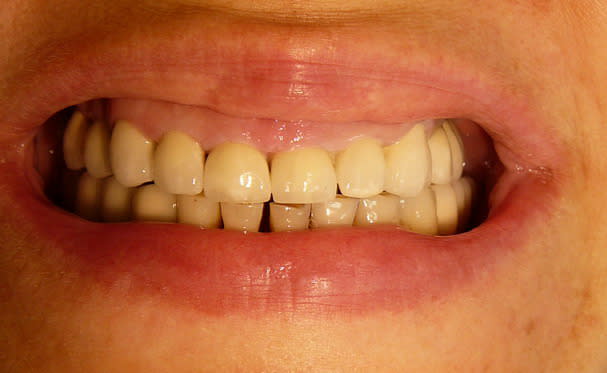

Avec un parodonte épais comme celui-ci, former la gencive n'est pas trop difficile.

With a gum biotype like this on, manipulating the gum is not very difficult.

Il y a aussi un gummy-smile et un sourire inversé, dommage après tant de couronnes.

The final result is a gummy smile with reverse smile line...too bad after all those crowns. A simple perio surgery could have give better result.